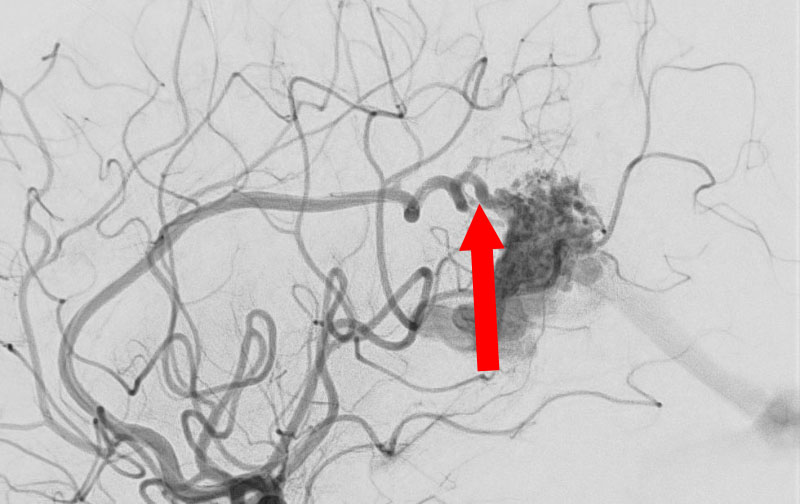

No.1576 手術前

No.1576 手術中

No.1576 手術後